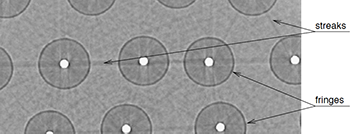

F. P. Vidal, J. M. Létang, G. Peix, and P. Clœtens.

Investigation of artefact sources in synchrotron microtomography via

virtual x-ray imaging.

Nuclear Instruments and Methods in Physics Research B,

234(3):333-348, June 2005.

F. P. Vidal, J. M. Létang, G. Peix, and P. Clœtens.

Investigation of artefact sources in synchrotron microtomography via

virtual x-ray imaging.

Nuclear Instruments and Methods in Physics Research B,

234(3):333-348, June 2005.

Qualitative and quantitative use of volumes reconstructed by computed tomography (CT) can be compromised due to artefacts which corrupt the data. This article illustrates a method based on virtual X-ray imaging to investigate sources of artefacts which occur in microtomography using synchrotron radiation. In this phenomenological study, different computer simulation methods based on physical X-ray properties, eventually coupled with experimental data, are used in order to compare artefacts obtained theoretically to those present in a volume acquired experimentally, or to predict them for a particular experimental setup. The article begins with the presentation of a synchrotron microtomographic slice of a reinforced fibre composite acquired at the European Synchrotron Radiation Facility (ESRF) containing streak artefacts. This experimental context is used as the motive throughout the paper to illustrate the investigation of some artefact sources. First, the contribution of direct radiation is compared to the contribution of secondary radiations. Then, the effect of some methodological aspects are detailed, including under-sampling, sample and camera misalignment, sample extending outside of the field of view and photonic noise. The effect of harmonic components present in the experimental spectrum are also simulated. Afterwards, detector properties, such as its impulse response or defective pixels, are taken into account. Finally, the importance of phase contrast effects is evaluated. In the last section, this investigation is discussed by putting emphasis on the experimental context which is used throughout this paper. Keywords: X-ray microtomography; Artefact; Deterministic simulation (ray-tracing); Monte Carlo method; Phase contrast; Modulation transfer function |